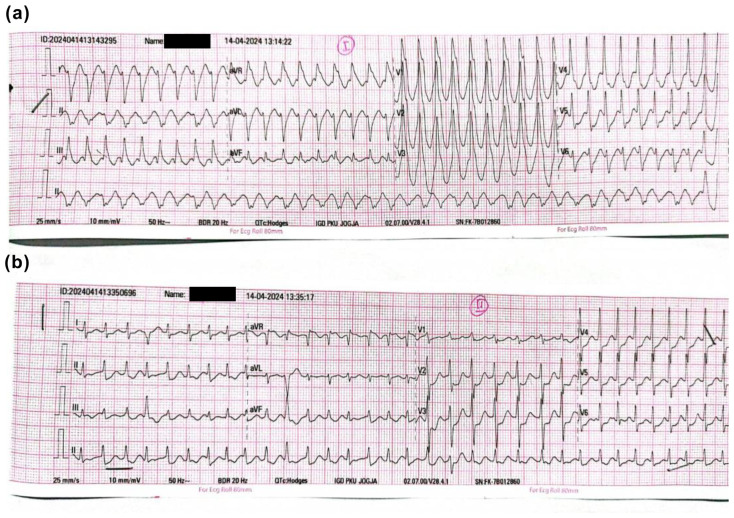

Identifying the infarct-related artery (IRA) in a non-ST-segment-elevation acute myocardial infarction (NSTEMI) can be very challenging, particularly in a hospital that cannot perform intracoronary imaging due to certain limitations. This is because, by angiography, most patients present with multivessel coronary artery disease (CAD), diffuse disease, or non-significant CAD. We present a case of a 60-year-old female patient presented with substernal chest pain and palpitations of 6 h duration. The first hospital contact 12-lead electrocardiogram (ECG) showed ventricular tachycardia (VT) with unstable hemodynamics, after stabilization patient was transported to the catheterization laboratory for immediate percutaneous coronary intervention (PCI). With a clue of VT morphology, post-converted ECG, and coronary angiography, the patient successfully underwent PCI in the left circumflex artery.